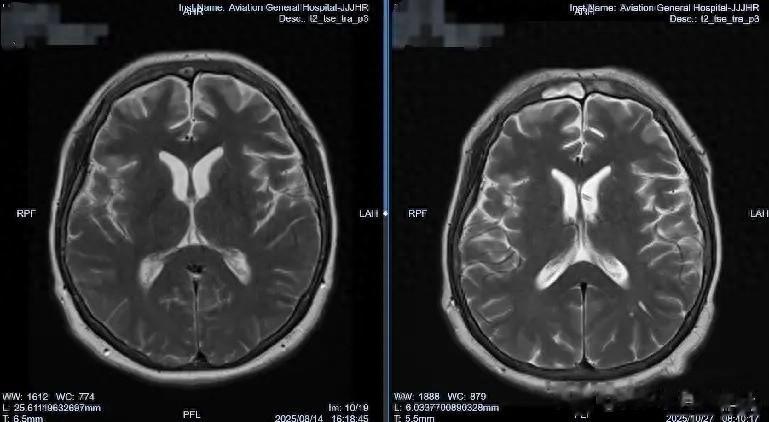

肖庆主任决定采取分阶段治疗策略:首先在2025年8月13日进行“腰大池置管引流”,建立初步引流通道;随后在8月21日实施“脑室腹壁外引流术”,建立持续引流通道。“精准的脑脊液管理是真菌性颅内感染治疗的关键。”肖主任强调,“我们不仅要控制感染,更要通过精细的引流调节,维持正常的颅内环境,为大脑恢复创造最佳条件。”

当引流管夹闭一周后,李女士没有出现任何不适,医疗团队知道,他们的治疗策略奏效了。2025年10月28日,肖庆主任为李女士成功结扎了引流管。那一刻,病房里洋溢着久违的轻松气氛。